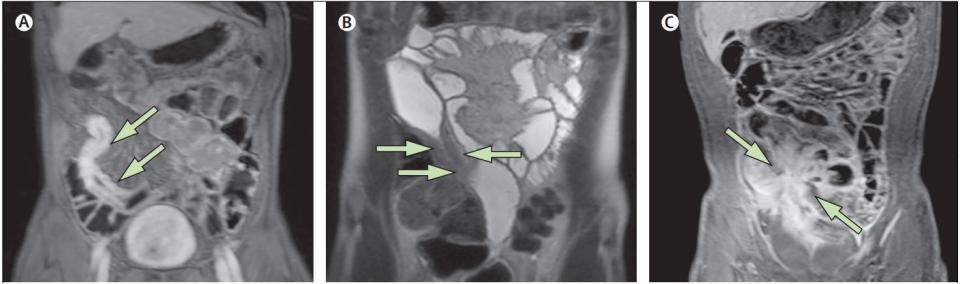

Болезнь Крона: МР-энтерография